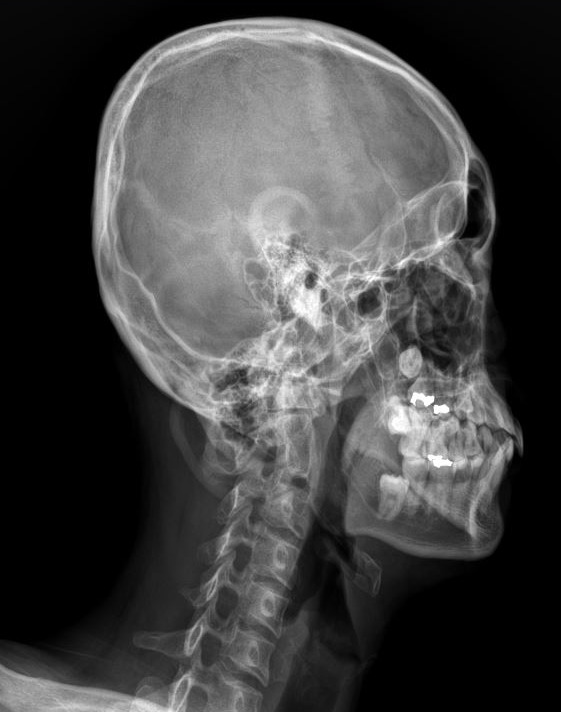

아래턱이 교합 문제나 경추의 아탈구로 뒤로 밀리게 되면 비강에서 이어지는 airway는 좁아지게 됩니다. 아래 엑스레이 사진을 보면 왼쪽 영상의 경우 정상에 가까운 airway 상태이며 오른쪽은 하악이 후방 이동하면서 airway가 좁아져 있는 것을 보여주고 있습니다. 실제로 오른쪽 환자의 경우 심한 비염 증상과 함께 코골이와 수면 무호흡증으로 양압기를 사용하고 있었으며 만성적인 뒷목, 어깨 통증과 함께 얼굴비대칭과 턱관절 장애가 동시에 진행되어 있습니다.

아래턱의 위치에 따른 airway의 변화 ( 왼쪽 : 정상 / 오른쪽 : 좁아진 airway)

이 엑스레이 영상에서는 뒤로 밀려있던 턱이 앞으로 이동하면서 airway의 직경이 개선되는 것을 확인해볼 수 있습니다.